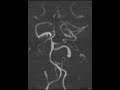

Persistent Trigeminal Artery

These images demonstrate a vascular structure arising from the junction of the petrous and cavernous segments of the left internal carotid artery which forms an anastomosis with the basilar artery. The vertebrobasilar system is relatively hypoplastic as well as the P1 segment of the right posterior cerebral artery. Findings are compatible with a persistent trigeminal artery which is found in less than 1% of cerebral angiograms and has an association with intracranial aneurysms. The shape has been likened to the greek letter tau.